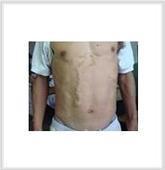

先天性血管瘤

628健康网为您分享有关先天性血管瘤的症状,先天性血管瘤的治疗方法,先天性血管瘤的预防知识,先天性血管瘤的症状图片,先...

小儿血管瘤

628健康网为您分享有关小儿血管瘤的症状,小儿血管瘤的治疗方法,小儿血管瘤的预防知识,小儿血管瘤的症状图片,小儿血管瘤...